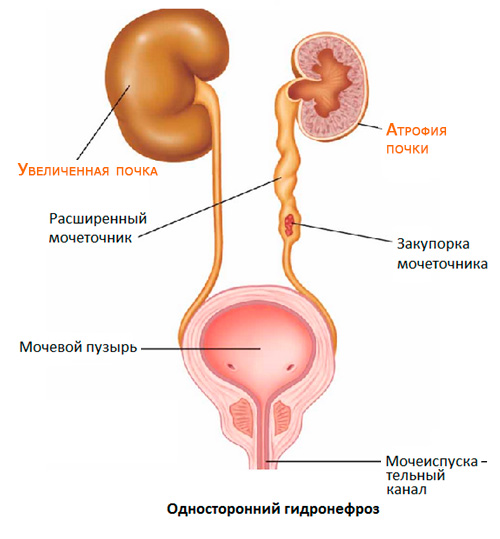

Рефлюксирующий мегауретер: Визуализация и медицинские изображения

Раздел: Фотопуть к знанию